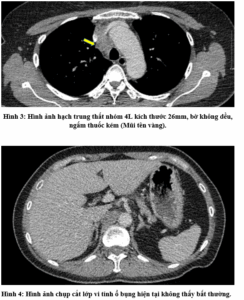

CASE LÂM SÀNG: CHẨN ĐOÁN BỆNH NHÂN ĐỒNG MẮC BA LOẠI UNG THƯ TẠI TRUNG TÂM Y HỌC HẠT NHÂN VÀ UNG BƯỚU, BỆNH VIỆN BẠCH MAI

CASE LÂM SÀNG: CHẨN ĐOÁN BỆNH NHÂN ĐỒNG MẮC BA LOẠI UNG THƯ TẠI TRUNG TÂM Y HỌC HẠT NHÂN VÀ UNG BƯỚU, BỆNH VIỆN BẠCH MAI GS. TS. Mai Trọng Khoa, PGS. TS. Phạm Cẩm Phương, PGS. TS. Phạm Văn Thái, BSNT. Đỗ Thị Thu Trang Trung tâm Y...